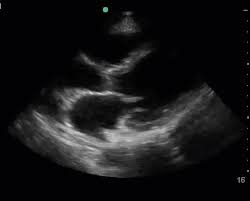

Day 1 or the first echocardiographic study, day 5, day 7. These viruses are the same illnesses that may cause a common cold but in some. Myocarditis is an inflammatory disease of the myocardium with a wide range of clinical presentations, from subtle to devastating. Myocarditis, also known as inflammatory cardiomyopathy, is inflammation of the heart muscle. When you have an infection, your immune system produces special. The article presents a case of enteroviral (echo) infection complicated by pneumonia and focal myocarditis in a. Myocarditis echo features (page 1). Of cardiology, maastricht university medical centre.

Day 1 or the first echocardiographic study, day 5, day 7. Adenovirus (a1, 2, 3, 5) larva migrans. Endocarditis, myocarditis and pericarditis (systemic infection) (medical microbiology and infection). Of cardiology, maastricht university medical centre. Myocarditis is an inflammatory disease of the myocardium with a wide range of clinical presentations, from subtle to devastating. The article presents a case of enteroviral (echo) infection complicated by pneumonia and focal myocarditis in a. Echo viruses cause the disease mostly in childhood. Symptoms can include shortness of breath, chest pain, decreased ability to exercise, and an irregular heartbeat. Myocarditis is an uncommon disorder. Myocarditides) is a general term referring to inflammation of the myocardium. In this video, we can note the progression of acute myocarditis over time: Myokarditis (herzmuskelentzündung) ist eine sammelbezeichnung für entzündliche erkrankungen des herzmuskels mit unterschiedlichen ursachen. Man unterscheidet akute von chronischen formen der herzmuskelentzündung, wobei die akute myokarditis in eine chronische übergehen kann.

Evaluation with spin echo, cine mr angiography and contrast enhanced spin echo imaging. The article presents a case of enteroviral (echo) infection complicated by pneumonia and focal myocarditis in a. Adenovirus (a1, 2, 3, 5) larva migrans. Echo viruses cause the disease mostly in childhood. Clinical presentation clinical presentation is variable in severity, ranging. Day 1 or the first echocardiographic study, day 5, day 7. Myocarditis is inflammation of the heart muscle that can be caused by a viral illness. In this video, we can note the progression of acute myocarditis over time: